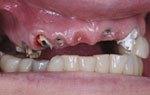

This method is mainly used for severely resorbed upper jaws and is designed to allow immediate replacement with fixed prosthetic teeth.

.Teeth are delivered in a maximum of three days. A crown can be placed over the implant within three days of placement.

• Eating hard food such as apples are also possible after three days post implant placement.